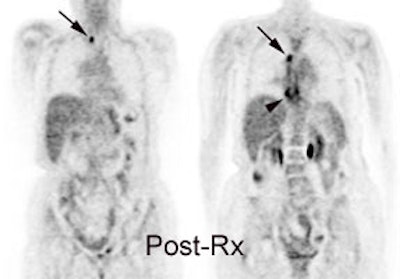

Response to therapy: This is the patient shown in the case above with progressive dysphagia and a large distal esophageal mass with gastrohepatic ligament adenopathy. Note the decreased uptake within the primary mass (arrowhead) and gastrohepatic nodes following initiation of radiation therapy. However, new uptake can be seen in two lymph nodes (black arrows) which were not identified prospectively on post-therapy CT imaging (white arrows on CT). The findings are concerning for metastatic disease and the patient went on to receive additional chemotherapy with subsequent resolution of the nodal uptake. |